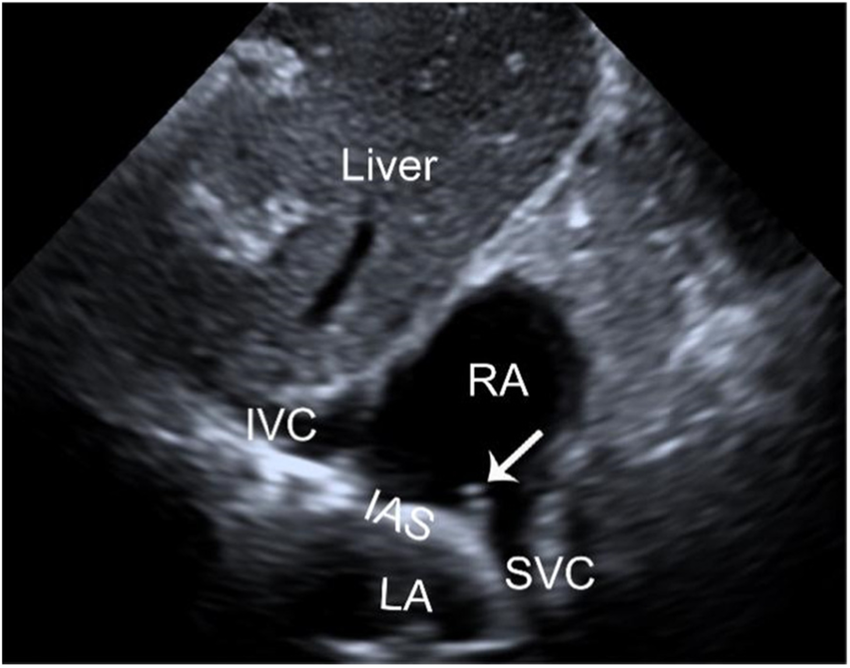

Draw and label subcostal short axis at IVC.

What is imaged though tilting the transducer in subcostal short axis? Sketch an image.

IVC/hepatic vein

RA

TV

Describe the Sniff test and its purpose.

Ask the patient to sniff to collapse the IVC

Measure the diameter of the IVC and its collapsibility index to assess RA pressure

How much does the IVC collapse during the sniff test with a healthy RA? What is expected with an unhealthy RA?

Healthy - collapse more than 50%

Unhealthy - collapse less than 50%